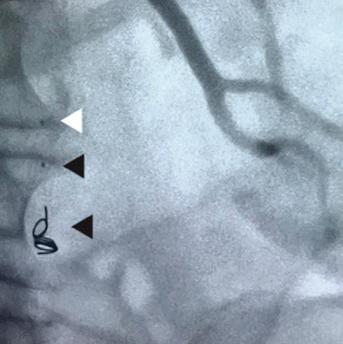

At ESVS 2022, Joost van Herwaarden (Utrecht University Medical Center, Utrecht, The Netherlands), who disclosed a research collaboration with Philips, spoke on the benefits and drawbacks of some of these technologies, speaking first on robotic navigation. He highlighted its ability to reduce radiation exposure for the operator and increase accuracy of catheter positioning, while acknowledging that the technology still carries the limitations associated with fluoroscopy use, due to its requirement for navigation.

Another technology is intravascular ultrasound (IVUS). “You get circular information about the vessel wall, the lumen, and also about aortic side branches, as well as improved arterial wall and stenosis characterisation, and improved sizing for your percutaneous transluminal angioplasty,” he said, noting however that visualisation length is limited to the ultrasound transducer, which is “why you still need fluoroscopy for navigation of your endovascular devices” with the use of IVUS.

According to Van Herwaarden, electromagnetic tracking addresses the limiting factors of greyscale images, offering instead brightly coloured images, as well as 3D navigation of devices, unlimited viewing angles, and no radiation, with the limited numbers of wires and catheters being a drawback.

Fiber Optic RealShape (FORS) technology from Philips also shows potential in this space, offering the benefits of 3D navigation, unlimited viewing angles, and the radiation-reducing benefits associated with the use of light instead of fluoroscopy, Van Herwaarden highlighted. He noted that one drawback is the fact there are only a limited number of devices available.

Finally, the presenter gave an overview of the pros and cons of image fusion. He stated that there is one system in this space—the Cydar Medical system—that offers automated registration. This technology compares the anatomy visible on live fluoroscopy with anatomy of a preoperative computed tomography angiography

(CTA) and automatically produces 3D overlay, he explained. According to the presenter, this technology offers “a significant reduction of contrast agent and also reduction of procedure time,” despite having a somewhat “complex setup”. Image fusion is “widely available” and, in the presenter’s opinion, “should be used in all complex procedures”.

Van Herwaarden summarised that these technologies show radiation-reducing potential, the small number of available publications suggest that these techniques are “still minimally applied”. According to the presenter, the future of these technologies lies in their combined use. For example, he said that, while electromagnetic tracking and FORS are “still under development,” they do offer “an even greater promise for simplifying complex procedures and realising dose reduction for patients and for staff,” when used in combination with IVUS or a robotic navigation system.

“Performing endovascular interventions without any form of radiation is certainly the future,” he concluded.